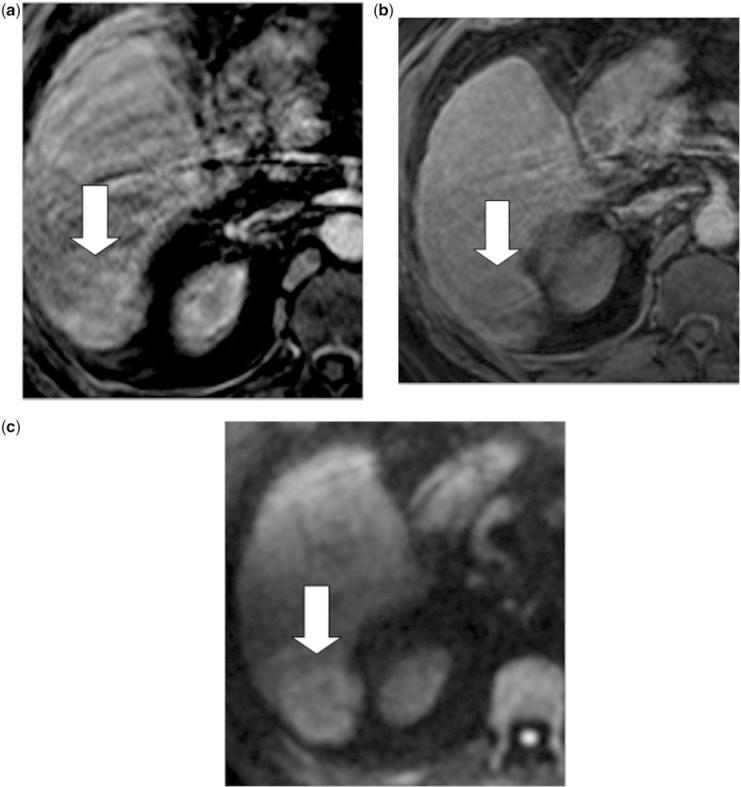

Diffusion-weighted imaging of the liver: an update.

Diffusion-weighted magnetic resonance imaging (DW-MRI) is now widely used as a standard imaging sequence for evaluation of the liver. The technique is easy to implement across different MRI platforms, and results in enhanced disease detection and characterization. With careful implementation, the quantitative apparent diffusion coefficient derived shows good measurement reproducibility, which can be applied for tissue characterization, the assessment of tumour response and disease prognostication. There is now a body of evidence that highlights the relative strengths and limitations of the technique for the assessment of liver diseases. The potential for more sophisticated analysis of DW-MRI data is currently being widely investigated.

扩散加权磁共振成像(DW-MRI)现在被广泛用作评估肝脏的标准成像序列。该技术易于在不同的 MRI 平台上实施,可提高疾病检测和特征描述的能力。通过仔细实施,所得到的定量表观扩散系数具有良好的可重复性,可用于组织特征描述、肿瘤反应评估和疾病预后预测。现在有大量证据强调了该技术在评估肝脏疾病方面的相对优势和局限性。目前,人们正在广泛研究对 DW-MRI 数据进行更复杂分析的可能性。